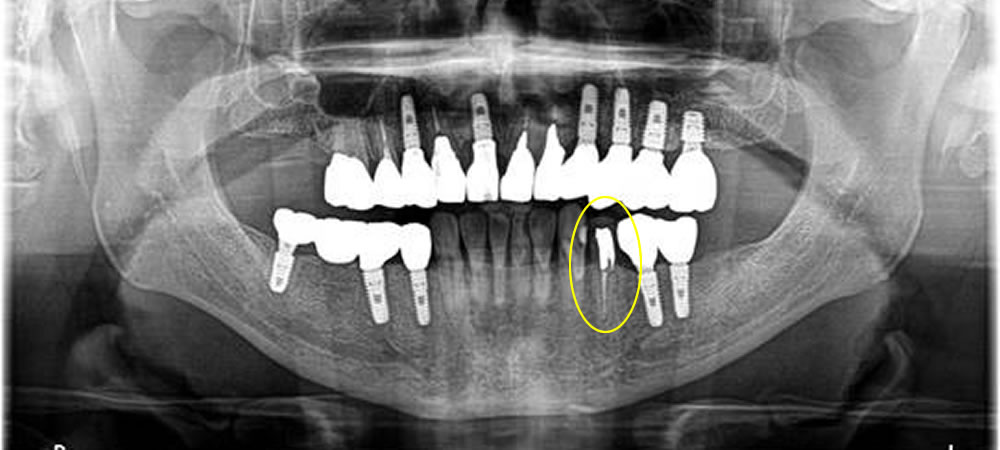

破折歯を抜歯後にインプラントで咬み合わせを回復した症例

年齢

70代

性別

女性

症例を見る